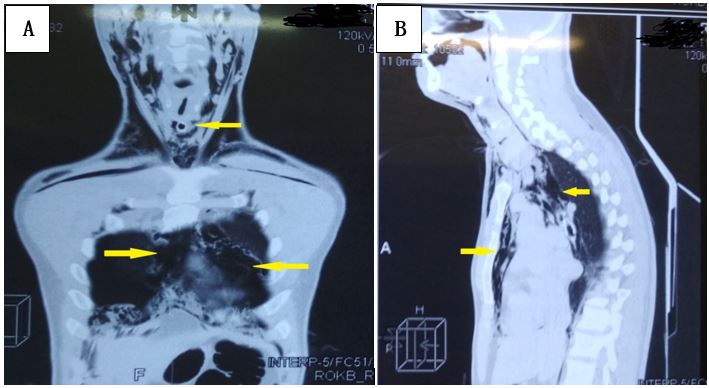

X-ray computed tomography (X-ray CT) was performed: parietal pneumothorax on both sides, pneumomediastinum, injury of the larynx, emphysema of the soft tissues of the neck and the chest wall (Figure 1).

Fig. 1. X-ray computed tomography of chest organs, frontal (A), and sagittal (B) projections. Em-physema of soft tissues of the neck, of the chest, is determined (pointed to by arrows). The tra-cheostomy tube is visualized